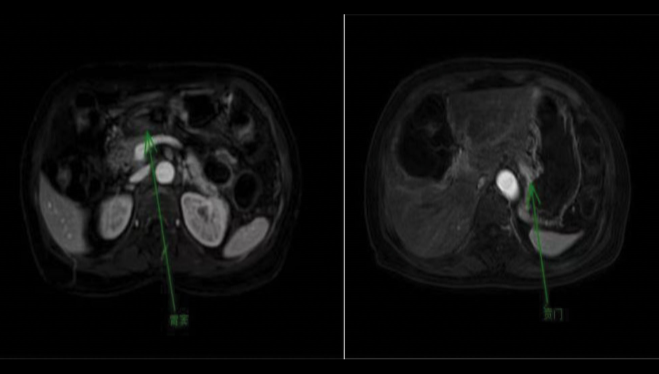

[cite: 64]上腹部平扫及增强MRI显示胃贲门及胃窦壁局部增厚并异常强化,无远处转移(cT2N1M0)(图4)。

图4. 影像学检查